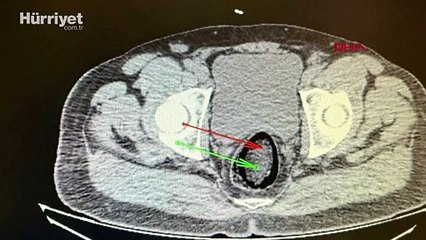

Kars'ta, jandarmanın durdurduğu yolcu otobüsünde hareketinden şüphelenilen İranlı 2 yolcudan 1'nin makatından diğerinin ise eşyaları arasından uyuşturucu çıktı. Kars'ın Digor İlçe İl Jandarma Komutanlığı ekipleri, Digor-Kars kara yolundaki uygulamada, yolcu otobüsünde arama yaptı.